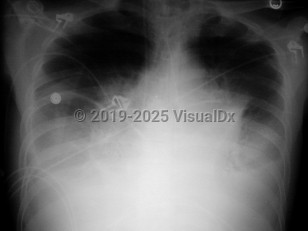

Pulmonary edema

Acute respiratory distress syndromeAcute respiratory distress syndrome